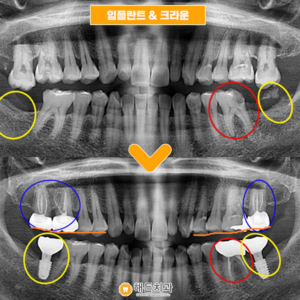

배방역치과 자연치아를 살리기 위해서는 (치료기간 : 2022.03~2022.06) 안녕하세요. 오늘은 저희 배방역치과를 내원하여 임플란트와 치관확장술을 통해 크라운치료하신 환자분을 소개해 드릴까 하는데요. 아래 사진을 보면서 설명해 드리도록 하겠습니다. 배방역치과 위 사진은 고*님의 치아 사진입니다. 고*님은 식사 때마다 통증을 느끼고 불편감을 느낀다고 하여 상담을 원한다고 하셔서 저희 치과에 내원해 주셨는데요, 더보기…